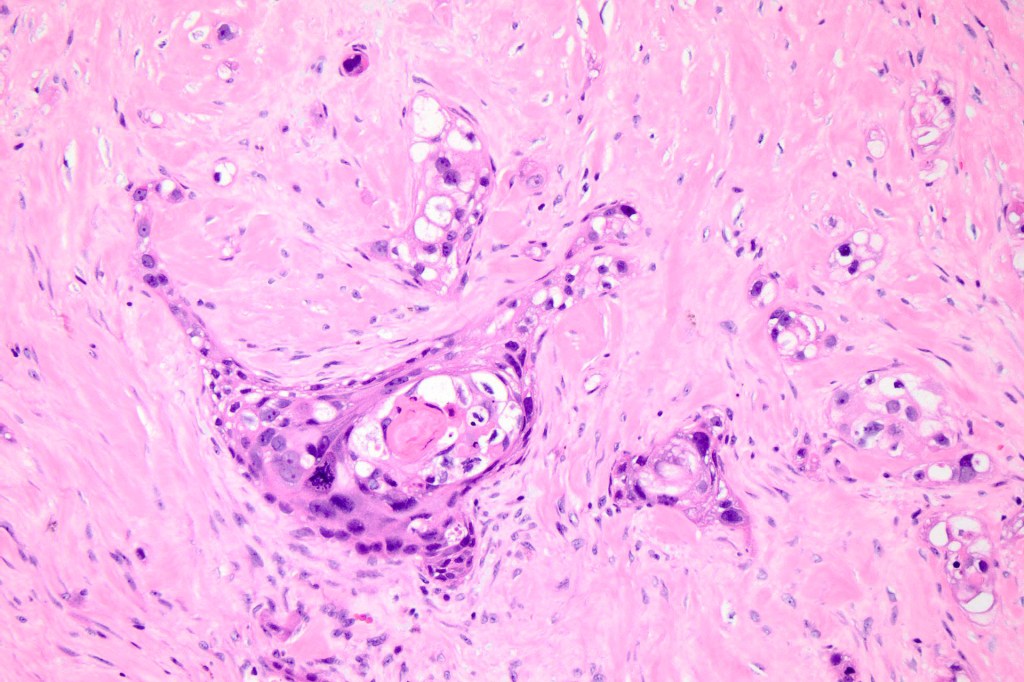

•Infiltrating tumor arising from the wall of a pilar cyst

•Malignant change within a proliferating pilar tumor

•Necrosis